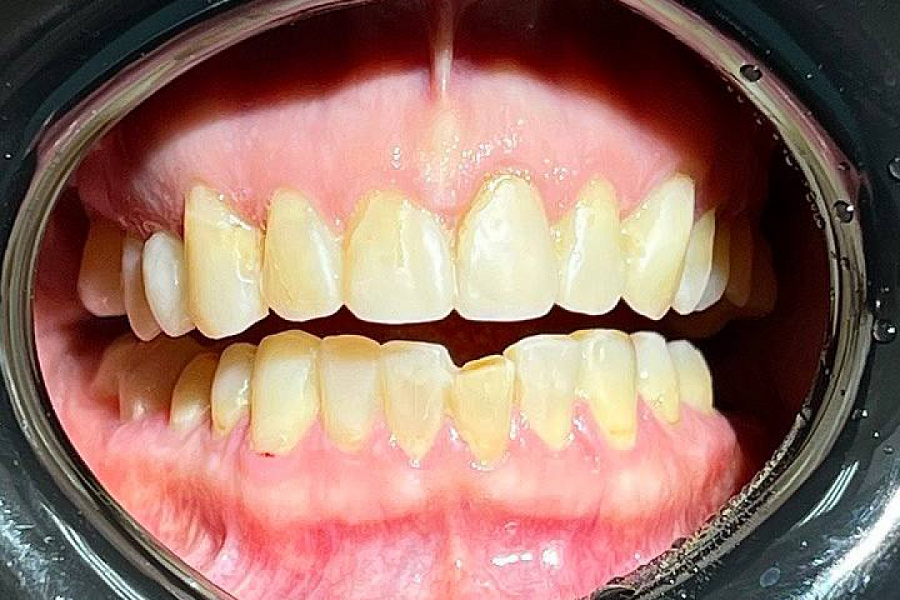

Пациентка обратилась с жалобами на неудобство и дискомфорт в области суставов. Диагностика выявила, что проблема связана с некачественным лечением и протезированием, которое вызвало снижение сустава нижней трети лица и изменение позиции других элементов ВНЧС.

1. Изготовили 3D-модели в новой терапевтической высоте.

2. Провели санацию зубов.

3. Далее сделали примерку будущих конструкций и на основании прототипа выполнили тотальное протезирование в новой терапевтической высоте в центральном соотношении челюстей.

После чего суставы встали в правильное положение, ушел дискомфорт при жевании, а лицо стало более подтянутым (антиэйдж стоматология в действии!)